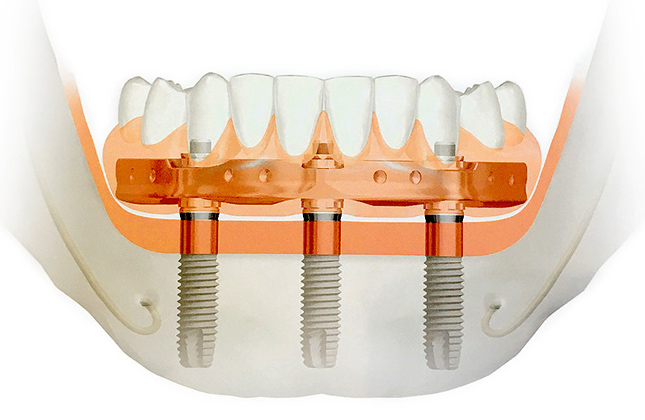

Apatinio bedančio žandikaulio implantavimas ant 3-jų dantų implantų per vieną dieną už beveik perpus žemesnę kainą. Tai naujausias svarbus išradimas – sąlyginai įvardinta „visi ant 3-jų“ dantų implantavimo sistemos kūrėjų ir pacientų svajonė, tapusi realybe. Nuolatiniai viso apatinio žandikaulio dantys per vieną dieną ypač aktualu gyvenantiems toli nuo implantuojančios klinikos ir dar toliau – nuo savo šalies.

Visi ant 4 – viso bedančio žandikaulio dantų implantavimas ant 4 dantų implantų. Kauno klinika „Angitia“ šį originalų patentuotą švedišką metodą pradėjo taikyti viena pirmųjų Lietuvoje ir sėkmingai taiko iki šiol. Eilė implantų gamintojų šią idėją pradėjo realizuoti tik po kelių metų, visiškai įsitikinę neabejotina šios sistemos kokybe. Tačiau tik švediškųjų dantų implantų „Visi ant 4“ metodika yra geriausiai ištirta ir dokumentuota nuo 1990 m., o „Angitia“ klinikoje sėkmingai taikoma nuo 2006 m.